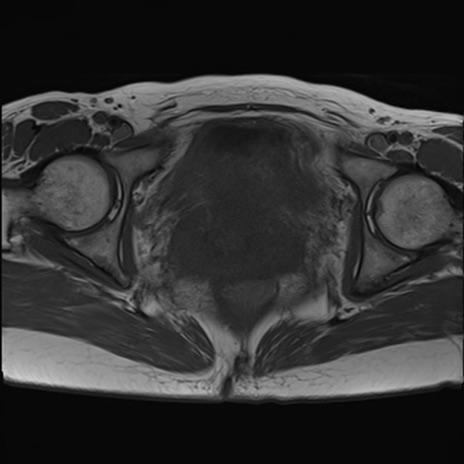

症例39 T1WI(横断像)

MRI(4日後)